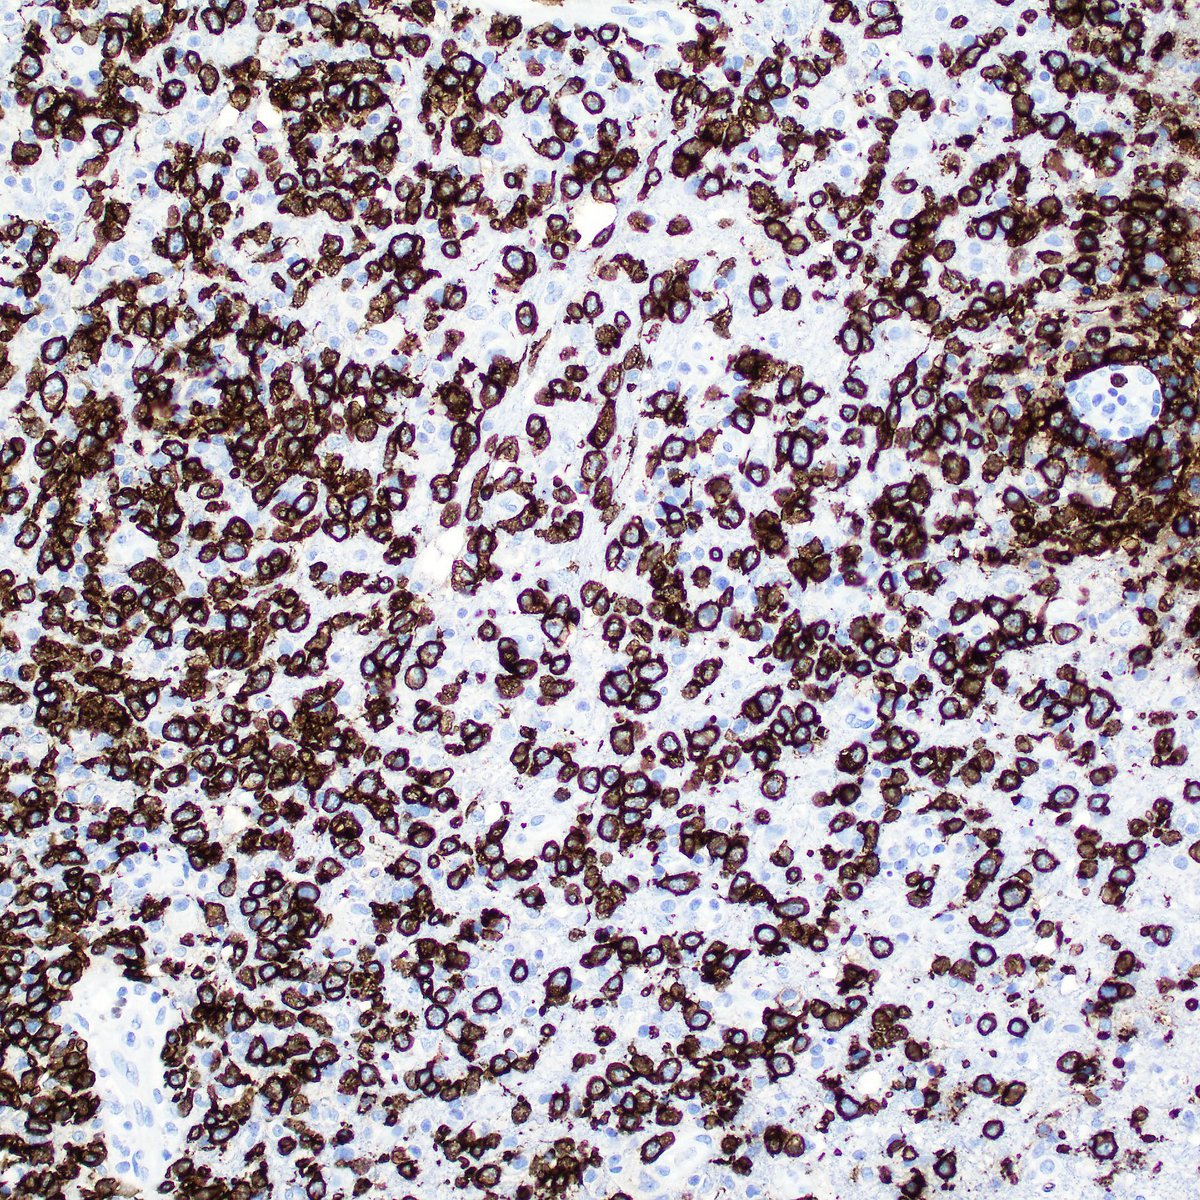

A good clue is the presence of lymphoglandular bodies in the background. Smear prep is probably the best way to diagnose CNS lymphoma at frozen section. Here is the accompanying H&E permanent section and CD20. #PathTwitter #pathology #Neuropath #hemepath